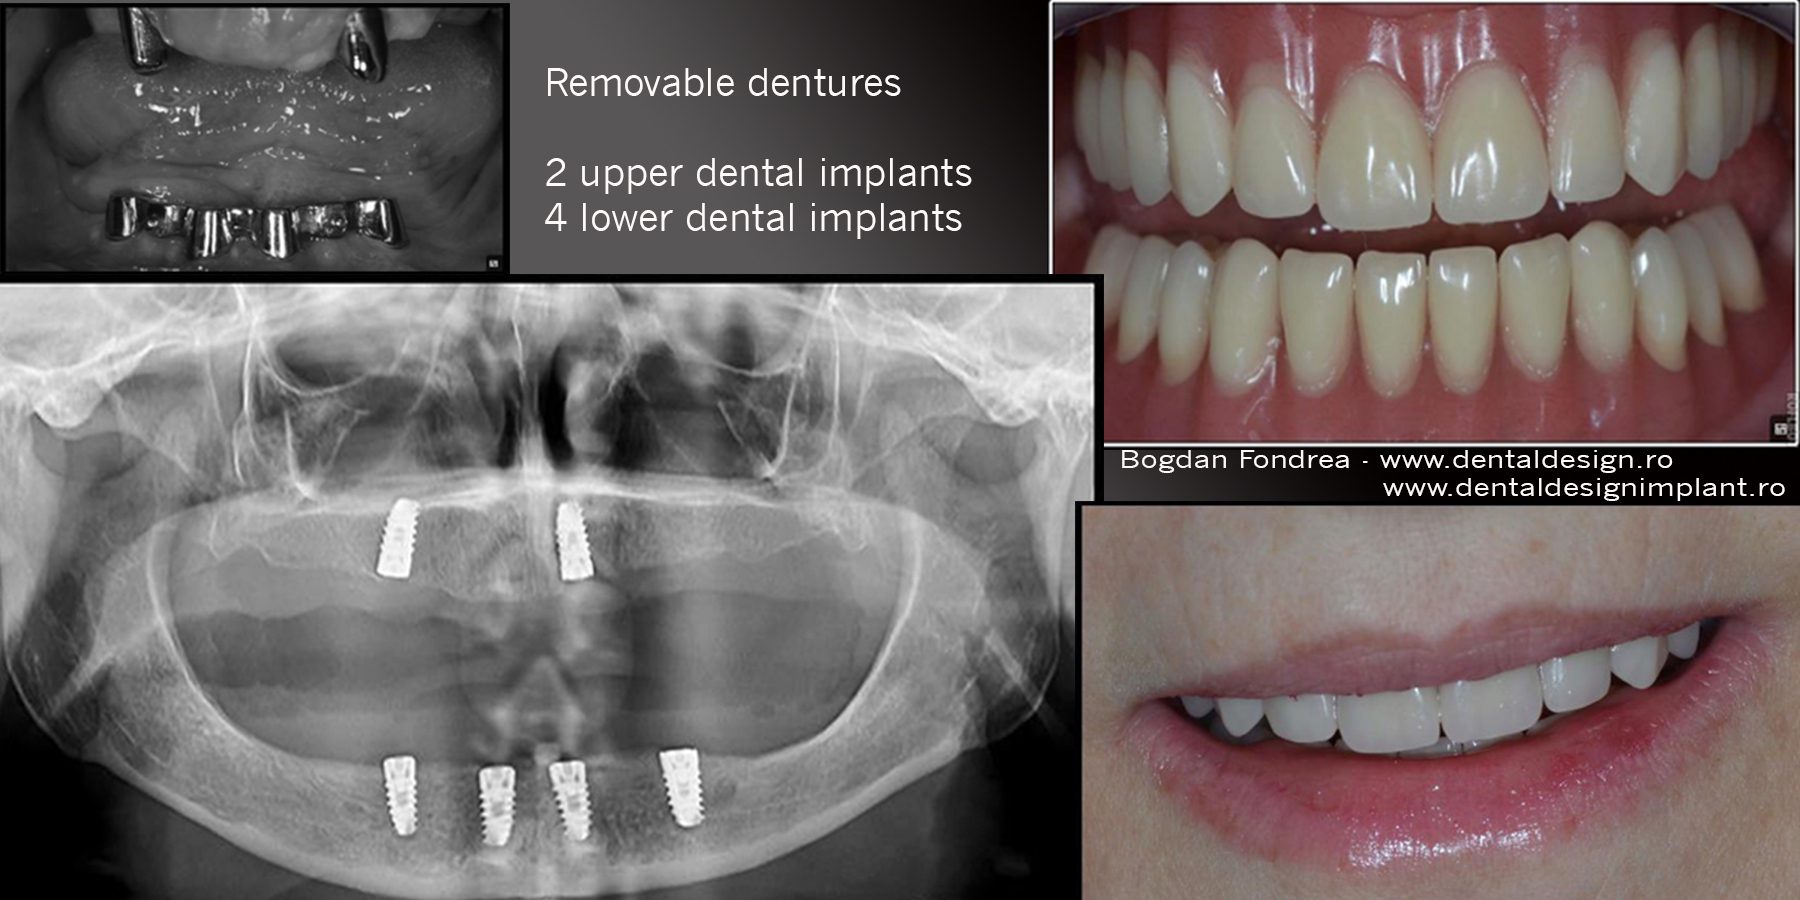

Avantajul acestora este că, față de protezele clasice, dau o mai mare siguranță, fiind ancorate prin intermediul implanturilor. Numărul de implanturi poate varia de la minimum două la patru-șase implanturi. Ele pot fi îndepărtate pentru igienizare și se reaplică. Față de lucrările fixe, au un cost mai mic și presupun o intervenție mai simplă, dar nu au avantajele acestora din urmă. Există mai multe sisteme de retenție: cu bilă, cu capse, cu bară, cu telescoape, cu magneți, în funcție de numărul de implanturi și de fiecare caz în parte, putând opta pentru varianta ideală. În imaginea următoare, pe partea superioară se vede un sistem de telescoape cu două implanturi, iar pe partea inferioară, un sistem cu bară și patru implanturi.